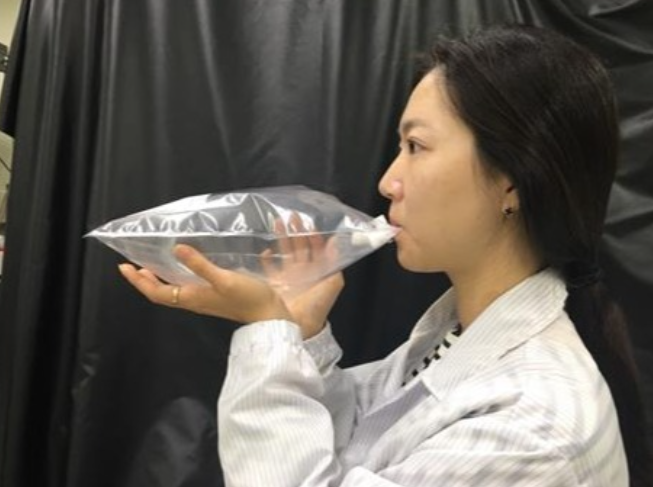

검사 방법도 간단하고 편리해요. 검진자가 날숨을 담은 비닐에 작은 탄소튜브 막대기를 연결하면, 우리가 내뱉은 호흡 중에 나오는 여러 가스들이 막대기에 붙어요. 그 다음, 이 막대기를 시스템에 넣으면, 시스템 내에 있는 20종의 센서가 그 가스 성분들을 분석하고, 전기 신호로 결과를 보여줍니다.